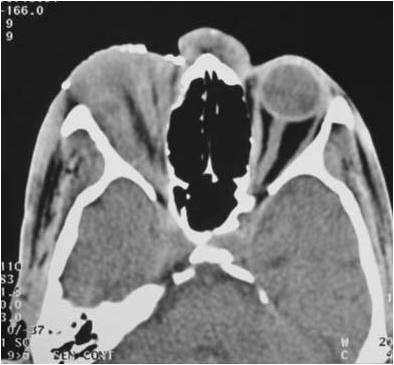

Radiograficamente, além do planejamento para os implantes, são avaliados todo o trajeto do nervo alveolar e a posição do forame mentoniano, utilizando-se da ortopantomografia, ou ainda de tomografia computadorizada (16).

Pode-se com isso fazer um traçado predicativo do local das osteotomias e, na tomografia, avaliar densidade do osso medular, a espessura das corticais e, as medidas precisas da posição do canal mandibular em todo seu trajeto

Estudo radiográfico perfeito para a concretização da manobra cirúrgica, levando-se em consideração todos os detalhes da localização do plexo alveolar inferior e suas relações anatômicas (Figs. 2 e 3).

Figs. 2 e 3 – Aspecto radiográfico mostrando a perfeita localização do plexo alveolar inferior com as medidas corretas para a manobra cirúrgica com a localização do implante.